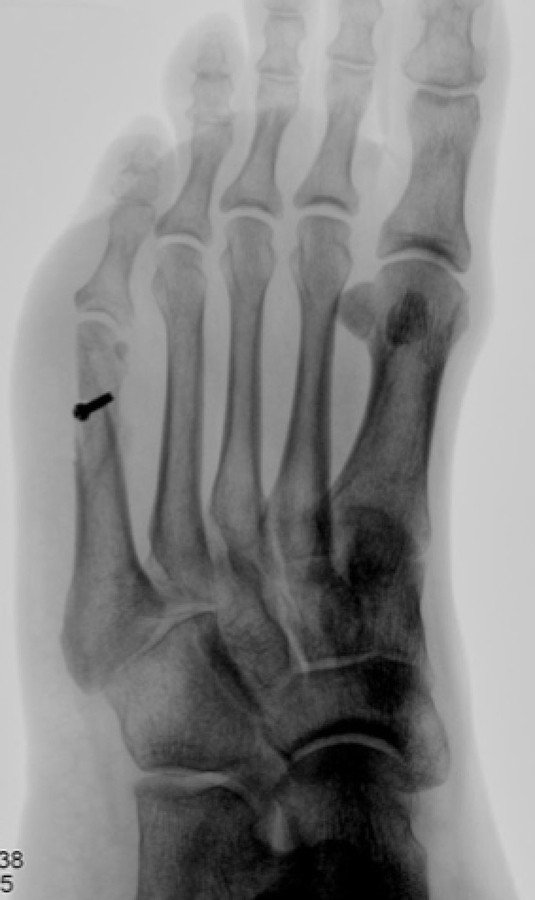

Röntgenaufnahme vom linken Fuss

Abb. 3: Röntgenaufnahme vom linken Fuss vier Wochen postoperativ: der «adduzierende», d.h. «heranführende» Knochenschnitt wurde mit einer Schraube fixiert. Es zeigt sich eine korrekte Stellung des 5. Mittelfussknochens mit beginnender knöcherner Durchbauung

Die Patientin entschied sich bei grossem Leidensdruck, den Eingriff machen zu lassen, wobei dieser und auch die Nachbehandlungsphase komplikationslos verliefen. Die Röntgenkontrolle vier Wochen postoperativ zeigte eine beginnende knöcherne Durchbauung des Knochenschnitts mit aufgerichtetem 5. Strahl, die korrekte Artikulation des Grundgelenks der 5. Zehe und die unveränderte Lage der einen Schraube, mit der der Knochenschnitt fixiert worden war. Somit war der Übergang auf Sportschuhe mit stabiler Sohle möglich, wobei der Fuss zwei Wochen lang noch nicht voll abgerollt werden sollte.

Anschliessend durfte die Belastung beschwerdeangepasst gesteigert werden. Bereits zweieinhalb Monate nach der Operation berichtete die Patientin über einen schmerzfreien und zufriedenstellenden Zustand ohne signifikante Einschränkungen im Alltag: sie war in der Lage, engere Schuhe anzuziehen, ihre 5. Zehe hatte guten Bodenkontakt, sogar die Missempfindungen in dieser Zehe waren verschwunden, womit wir nicht gerechnet hatten. Auch sportlich konnte sie sich wie gewünscht zunehmend engagieren – mit dem Joggen konnte sie etwa 4 Monate nach unserem Eingriff beginnen.